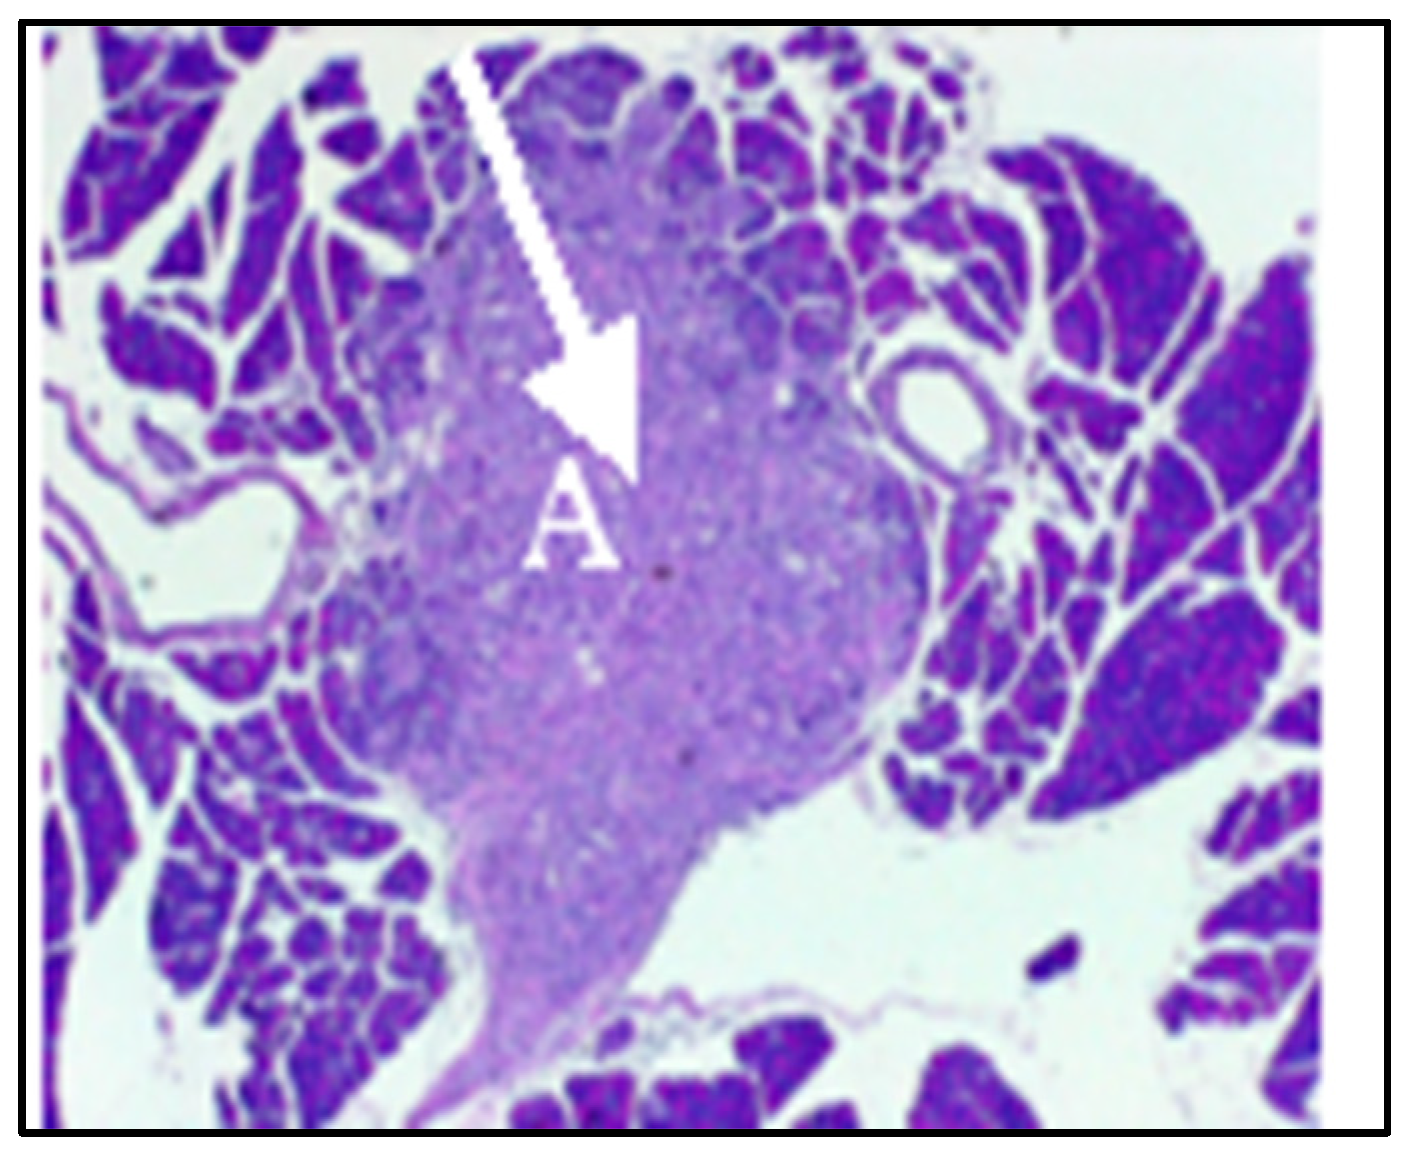

2.3. Effect of SV Vector on PDAC Models with Immunosuppressive TME